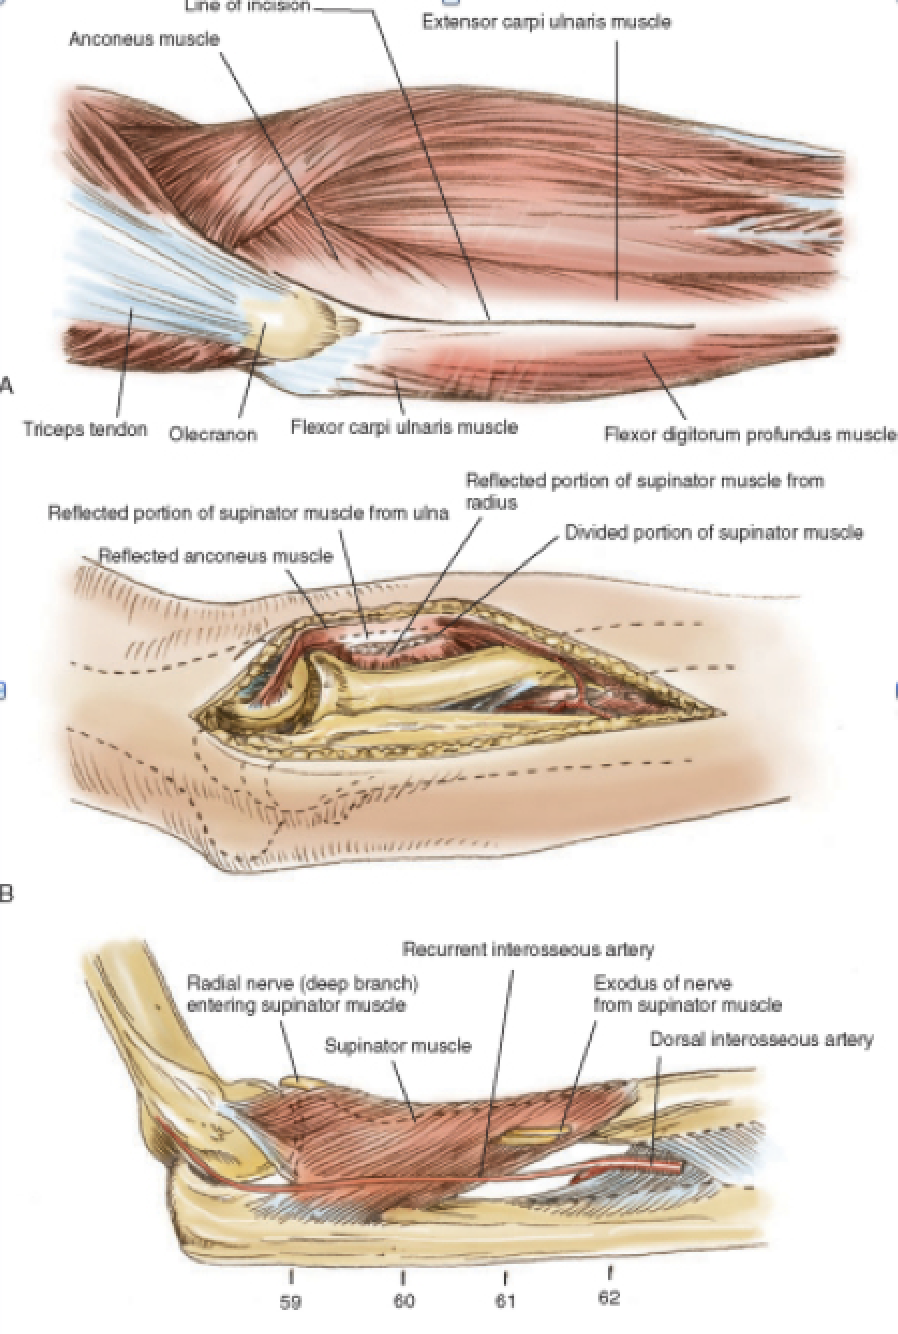

Boyd Approach

Interval: Between both anconeus (radial n.) and ECU (PIN), and subcutaneous boarder of ulna/ FCU (ulnar n.)

Approach: Develop interval between both anconeus and ECU, and lift both anteriorly. Release supinator subperiosteally.

Dangers: Increased risk of synostosis.